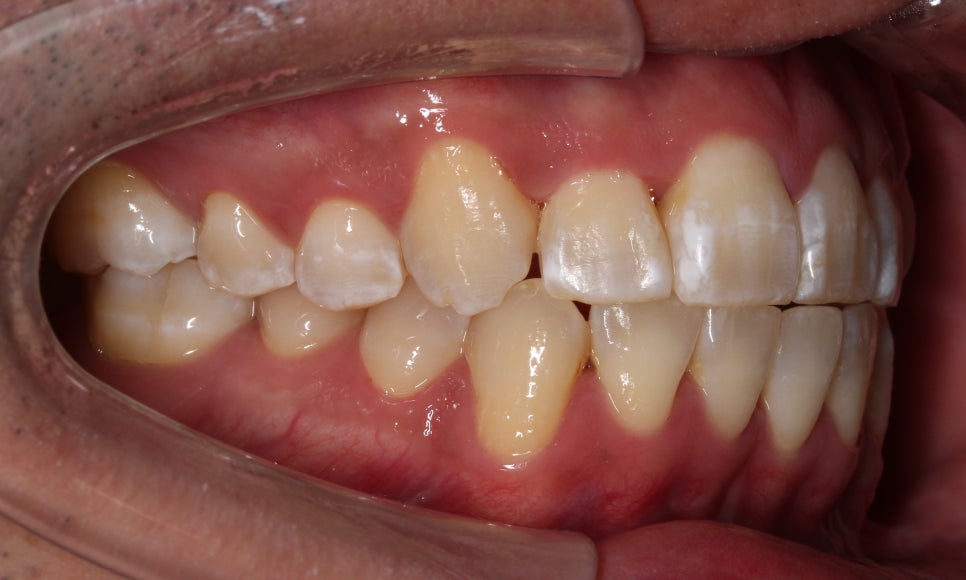

부분교정을 진행을 할 때에는

송곳니 위치와 구치부 교합관계를

꼭!!! 평가를 하는데요.

앞서 말씀드린 것처럼

송곳니 위치의 문제라기 보다

그 옆 치아가 상대적으로 들어가 있어서

덧니가 심해 보이는 모습이라,

제 기준으로는

충분히 부분교정이 가능해 보였습니다.

아래 앞니도 공간이 부족해서

약간 삐뚤빼뚤한 모습이 나타나지만

충분히 비발치 부분교정으로

펼칠 수 있는 케이스라 판단했습니다.

안 보이는 장치를 희망하셔서

2D교정으로 진행하기로 했습니다.